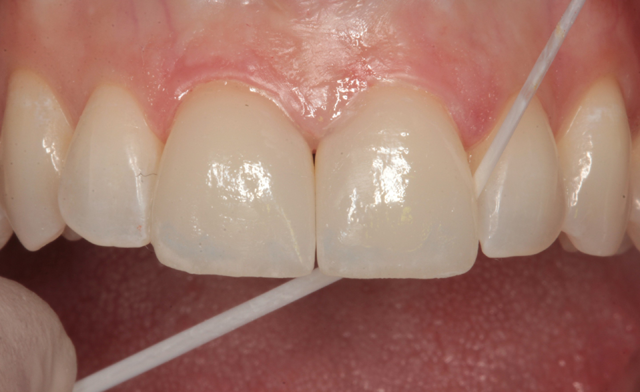

The LED curing light was used to “tack” the cement for two seconds each tooth (Fig. 20). A celluloid strip was eased through the interproximal area between veneers (Fig. 21) and floss was worked through the distal contacts to remove unset cement (Fig. 22). The LED curing light was used to complete the cure by exposing the facial and lingual surfaces for 20 seconds each Figure 23.

Fig. 20 Fig. 21 Fig. 22